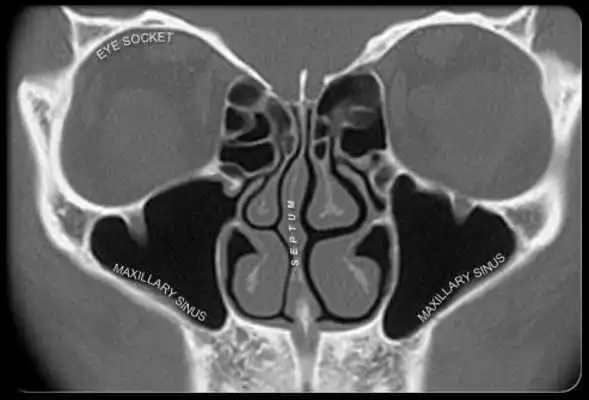

- What Are Sinuses?